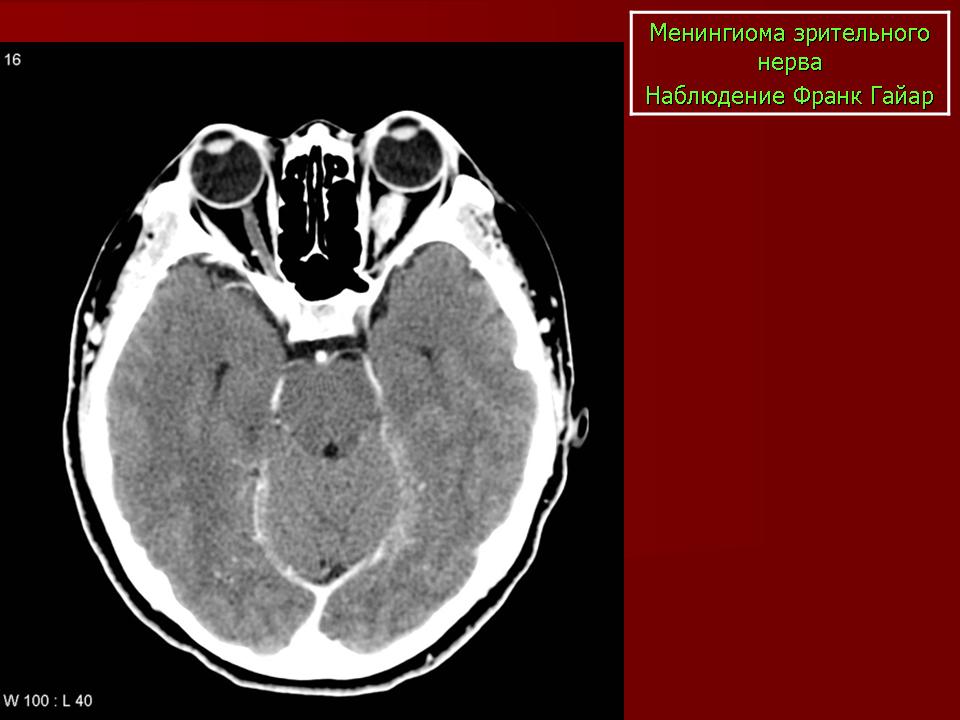

КТ-семиотика

На КТ срезах без контрастного усиления менингиома зрительного нерва выглядит изоденсной. Типично наличие линейных или точечных обызвествлений. Симптом «трамвайных рельс» отражает накопление КВ по сторонам гиподенсного зрительного нерва или наличие обызвествлений в структуре опухоли. Как правило, наиболее дистальная часть зрительного нерва, в месте его вхождения в глазное яблоко, не содержит обызвествлений.

При исследовании необходимо определить расположение бляшковидной менингиомы относительно бугорка турецкого седла и пластинки клиновидной кости, так как данный тип опухоли может распространяться интракраниально через канал зрительного нерва. КТ не позволяет адекватно визуализировать интракраниальное распространение опухоли, которое может привести к развитию двусторонней слепоты.